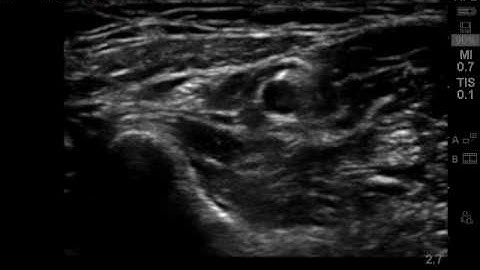

Superficial Radial Nerve Block